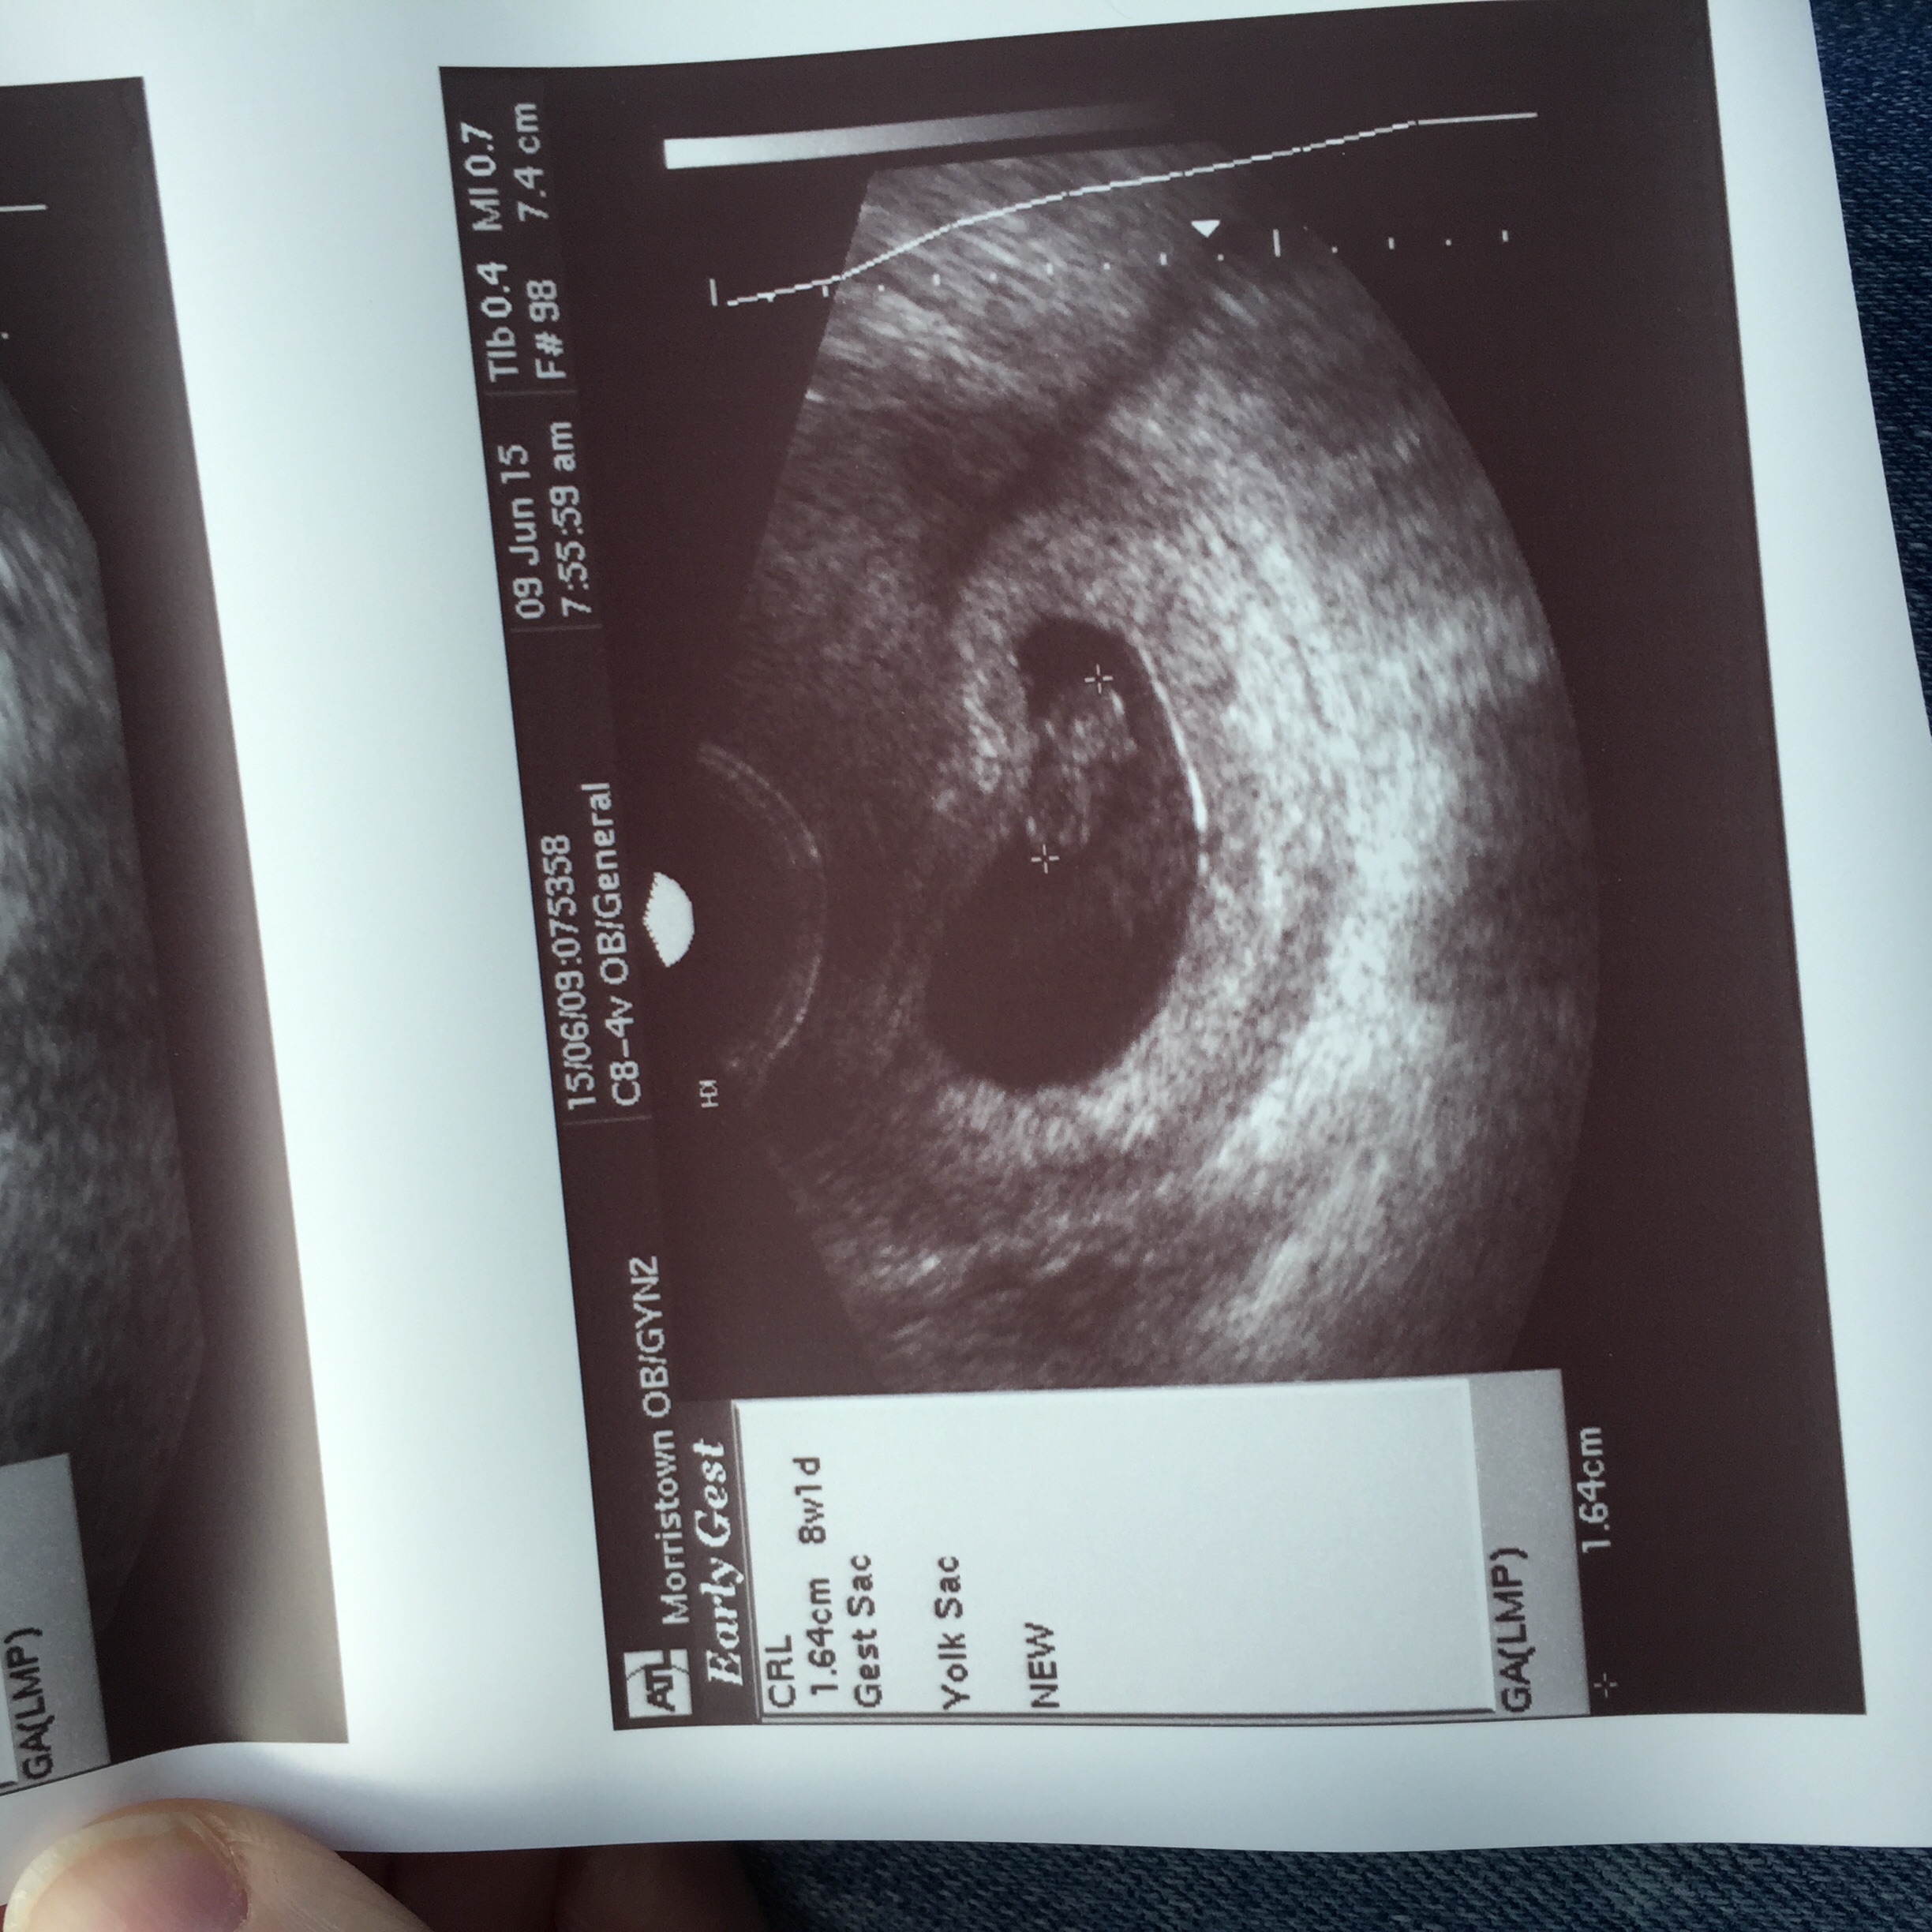

Is it the side the baby is on or the yolk sac or what? I read the placenta online, but I thought there wasn't placenta yet. My baby is kind of right in the middle but the yolk sac is definitely on the left.

This is my transvaginal ultrasound. Baby is in the middle but you can see placenta forming on the left which indicates a girl. Still don't know if it's accurate